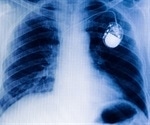

Implantable defibrillator cuts heart attack risk of sudden death by 31%